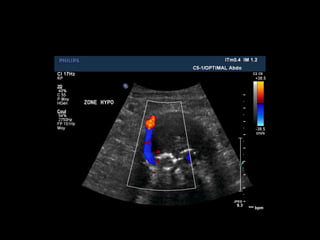

Doppler: caractéristiques hémodynamiques des endofuites

• flux entrant, sortant, alternant

• vitesses circulatoires à la porte d’entrée